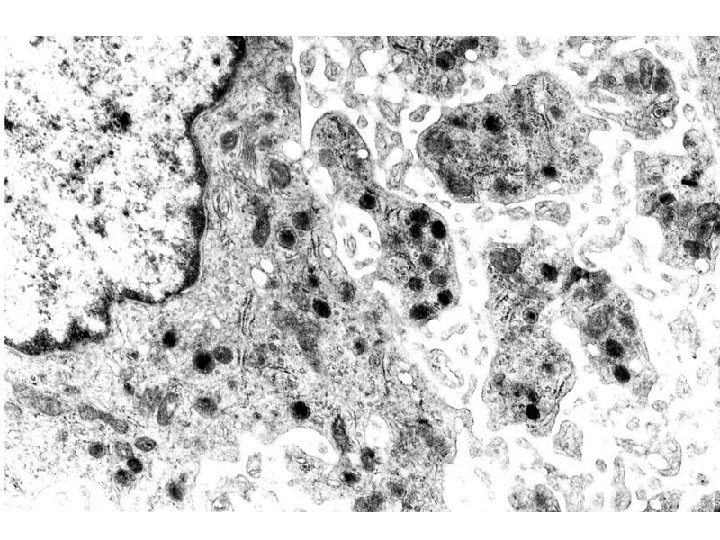

NORMAL platelet on LEFT, “DEGRANULATING” ALPHA GRANULE ON RIGHT AT OPEN WHITE ARROW

DIC